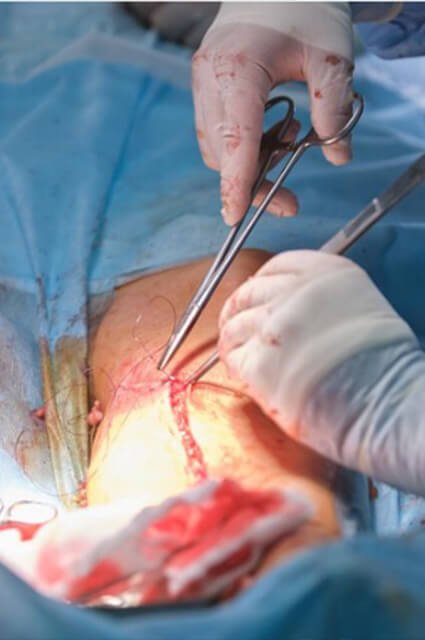

- جراحة المفاصل والتي تسمى أيضاً استبدال المفاصل، هي عملية جراحية لاستبدال المفصل التالف بمفصل صناعي مصنوع من المعدن أو السيراميك أو البلاستيك،

- وعادةً ما يقوم مقدمو الخدمة باستبدال المفصل بالكامل وفي كثير من الأحيان، يتم استبدال الجزء التالف من المفصل فقط،

- حيث يمكن إجراء الجراحة في عيادة خارجية أو في المستشفى ولكن تختلف التقنية التي يستخدمها الجراح اعتماداً على نوع الجراحة والمفصل الذي تحتاج إلى استبداله.

- يتم تخدير المريض قبل الإجراء وهذا يضمن بألا يشعر بالألم أثناء عملية تقويم المفاصل حيث يقوم الجراح بعمل جروح وإزالة المفصل التالف،

ثم يستبدلونه بمفصل صناعي ويستخدمون الغرز أو الدبابيس أو الغراء الجراحي لإغلاق الشقوق.